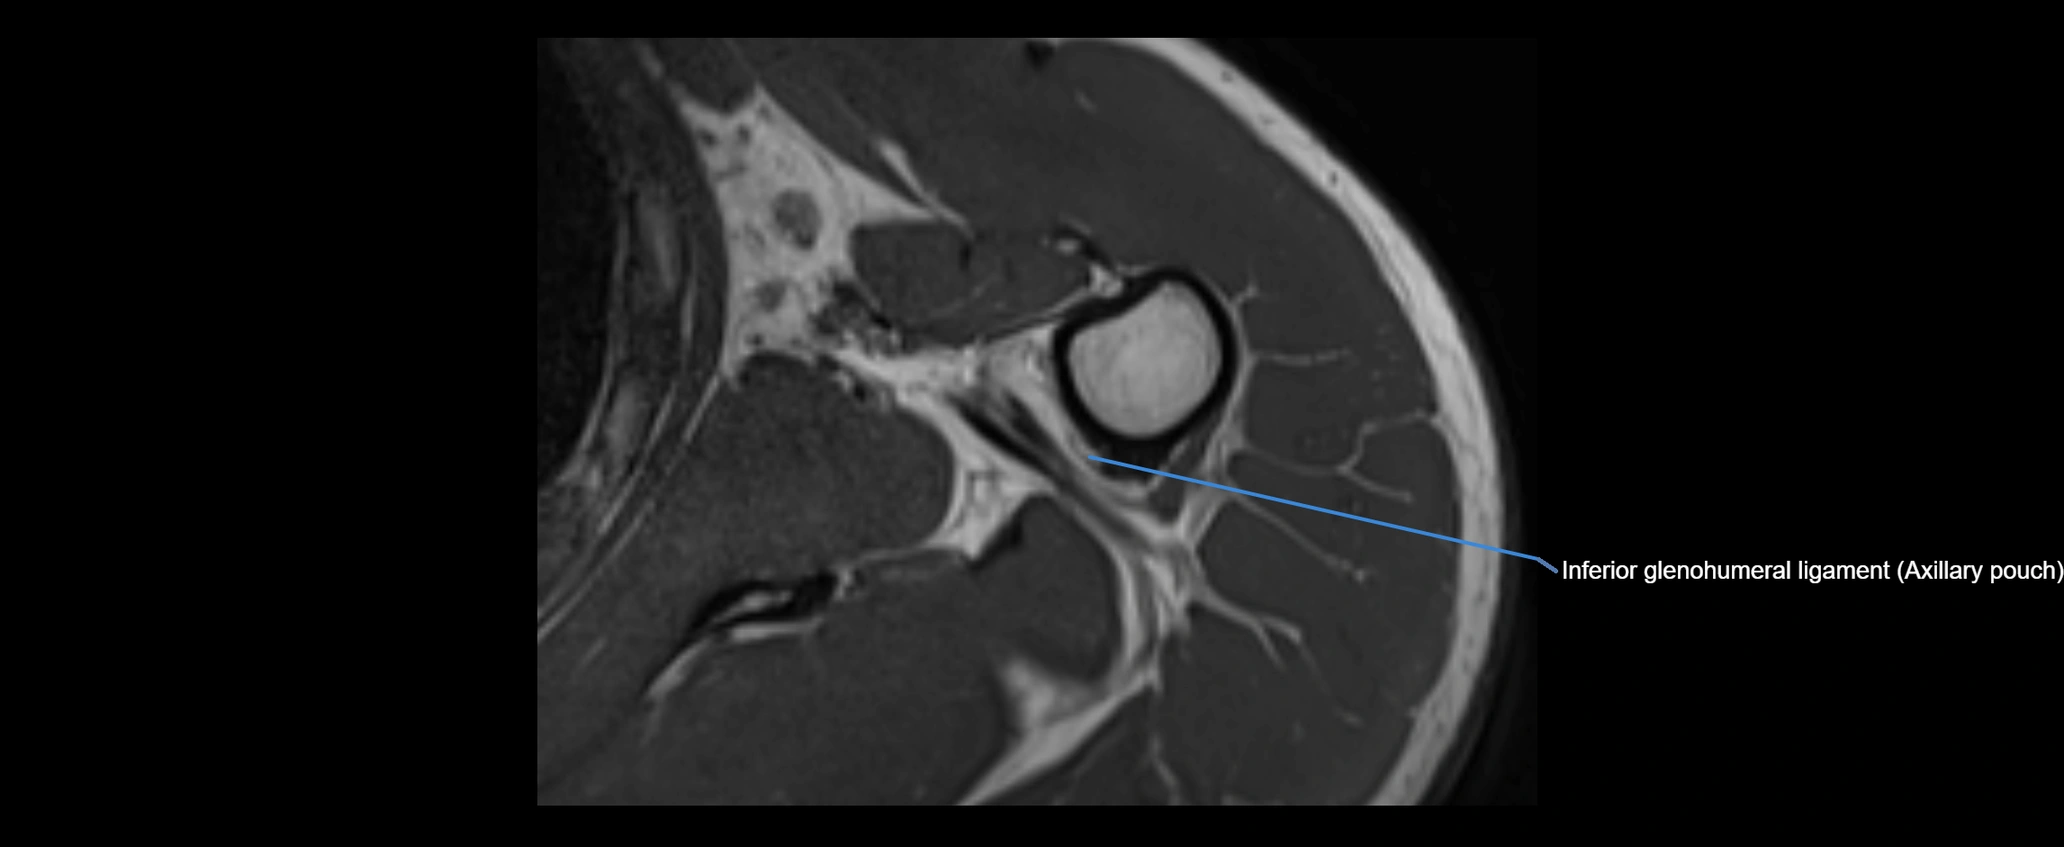

CT image

image